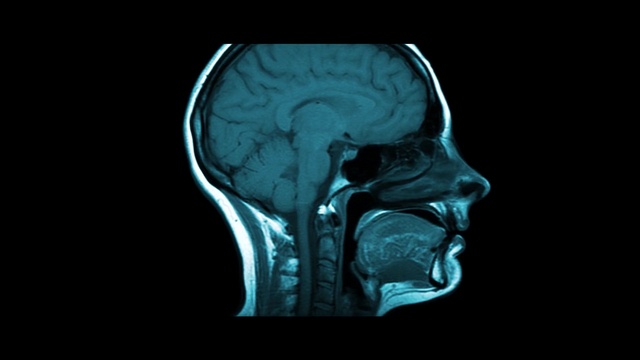

Best Video References: Migren